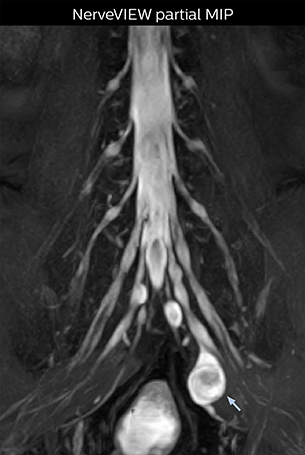

Northern Fukushima Medical Center (NFMC) Imaging Center uses the 3D NerveVIEW sequence for performing MR neurography, particularly in patients with pain and weakness in the lower limb. “It is included in about 20% of the approximately 150 lumbar spine MRI exams each month at NFMC, and can help us to determine if structures are impinging on the nerves,” says Hajime Tanji, RT, MRI technologist at NFMC.

“In such case, we would then browse through axial T2-weighted MR images slice by slice and mentally reconstruct the actual situation based on both radiculography and MRI. Fortunately, NerveVIEW can now very well show nerve courses and presence of nerve compression or edema in one single image series.” “We have often seen NerveVIEW directly depict details of the nerve compression that were not observed by radiculography. Therefore, we think that with NerveVIEW we can reduce the number of invasive examinations, especially for some patients with lumbar plexus symptoms.”

The key concept in MR neurography, Dr. Yabuki stresses, is the ability to directly visualize spinal nerves, versus inferring the presence of pathology indirectly. “Before NerveVIEW, we estimated compression of the nerve by looking for the presence or absence of fat signal on other MR images,” he says.

“For example, in sagittal images, when the presence of fat is observed in the intervertebral foramen, it suggests that there is a margin around the nerve. Similarly, the absence of fat indicates that the nerve is being compressed. So, we used to deduce nerve compression indirectly. With NerveVIEW, however, we can observe the condition of the nerves directly, regardless of the presence or absence of fat. We always prefer such direct observation of anatomy over having to make an inference about it.”

“NerveVIEW is really useful for those cases where a nerve disorder is strongly suspected based on the clinical examination but our regular MRI images do not show any findings. These atypical herniations and spinal canal stenosis, occurring in 5% to 15% of the total lumbar herniation/stenosis cases are our main target when using NerveVIEW,” says Dr. Yabuki.

“The intra-luminal signal of veins, especially around the intervertebral space, can be suppressed well with NerveVIEW. As a result, we can easily observe the detailed nerve structure around the posterior ganglion,” he says. “This is why we use 3D NerveVIEW for intraforaminal stenosis and extraforaminal stenosis/herniation (lateral disc herniation). On the other hand, if herniation is suspected to exist inside the dorsal root ganglion (DRG), balanced TFE or ProSet-FFE is applied. NerveVIEW is not suitable for evaluating the median type of herniation.” The SE-EPI DWI-based method for MR neurography works well for large FOV exams like whole-body MRI, but focal examination of nerves is often limited by the attainable spatial resolution (both inplane and slice direction) and geometric distortion. “3D NerveVIEW achieves higher in-plane resolution – close to our other routine spine sequences – and the source images can be used instead of adding a fat-suppressed T2-weighted sequence,” Tanji says.

Implementing NerveVIEW without lengthening exam time “The source images of NerveVIEW exhibit a contrast similar to STIR or fat-suppressed T2-weighted images. So, in our neurography exams we are replacing the 2D T2-weighted coronal sequence with 3D NerveVIEW. With this, we add a lot of useful information without adding scan time. This is important for patients with severe lower extremity symptoms, as they often find it difficult to maintain still during the whole MRI examination, so the exam should be as short as possible.” “We have currently implemented 3D NerveVIEW on our Achieva 3.0T dStream MRI system only. Because the 3D NerveVIEW method is based on a background signal suppression technique, we decided to use the high SNR of our 3.0T MRI system for obtaining the best possible visualization of peripheral nerves,” says Tanji. “Where NerveVIEW of the lumbar plexus is currently used as a subroutine scan for patients with strong lower limb symptoms, its use for visualization of the brachial plexus, is currently limited to special cases such as schwannomas and neuritis, usually only 1 or 2 cases per month.”